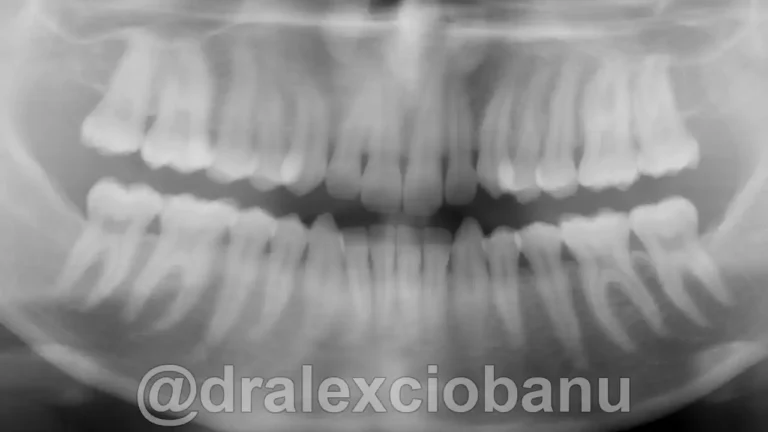

Il paziente presentava una malocclusione di prima classe per grave affollamento dentario superiore ed inferiore.

Al fine di garantire un alto livello di estetica e precisione maggiore nello spostamento dei denti, sono stati applicati degli attacchi linguali 3D WIN LINGUAL SYSTEM in entrambe le arrecate.

I brackets linguali possono allineare sia le corone che le radici dei denti, in modo che siano perfettamente posizionati l’uno accanto all’altro in posizione corretta. È spesso difficile ottenere questo posizionamento utilizzando gli allineatori rimovibili, specialmente quando si tratta di correggere le rotazioni dei canini. I brackets linguali fissi possono posizionare perfettamente i canini e i denti anteriori nella posizione corretta, come mostrato nella radiografia orto panoramica al termine della terapia.

La terapia ha richiesto tempi molto più brevi di una terapia con gli attacchi visibili o mascherine trasparenti.

Abbiamo corretto il morso ed ottenuto il perfetto allineamento dei denti.

Tempo totale di trattamento: 10 mesi.